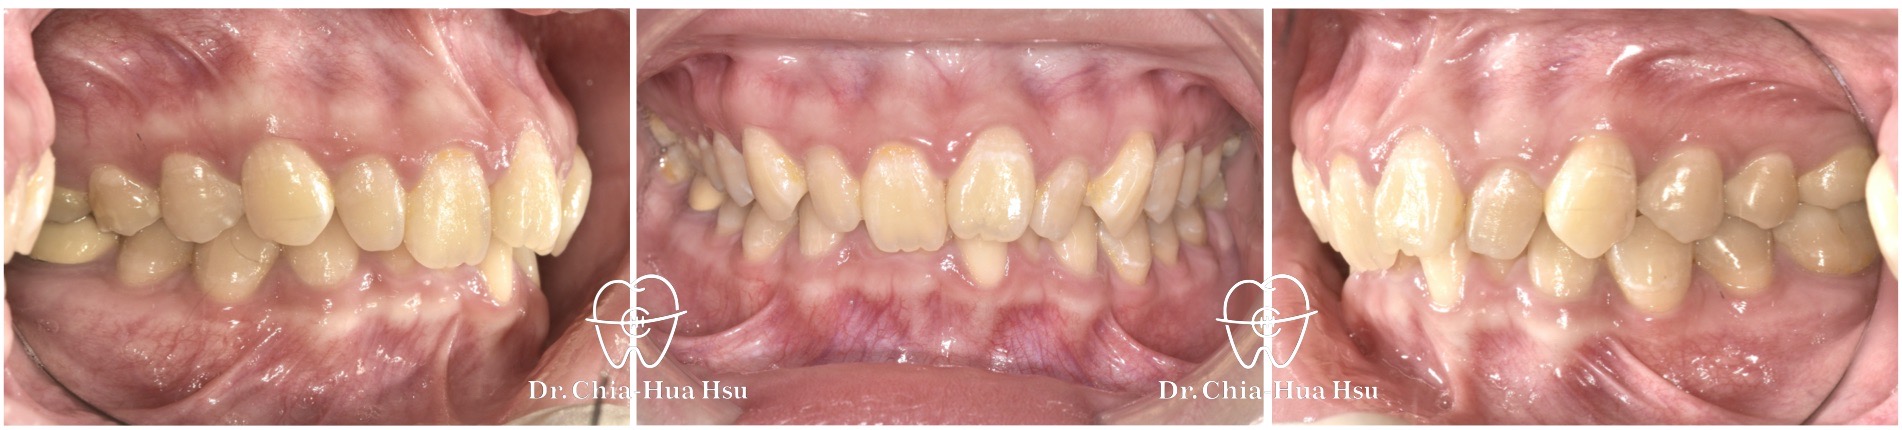

- 問題分析:患者是標準的骨骼一類咬合(Skeletal Class I)伴隨齒列擁擠以及深咬。

- 治療方式:使用傳統金屬矯正器,搭配二級橡皮筋牽引(Class II elastics)。

治療前